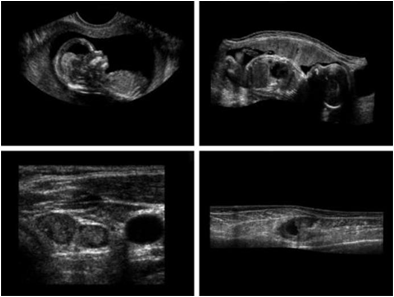

a)아기1 b)아기2 c)갑상선 d)손상된근육